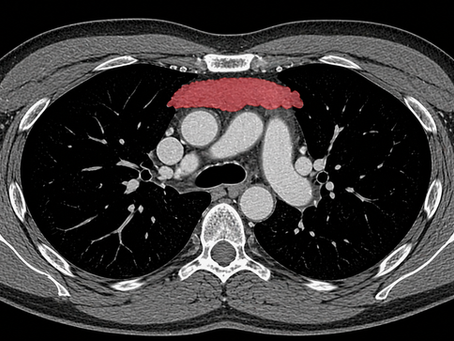

The Thymus and Long-Term Health

The thymus was thought to be irrelevant in adults. New data suggests it may predict disease risk and long-term survival.